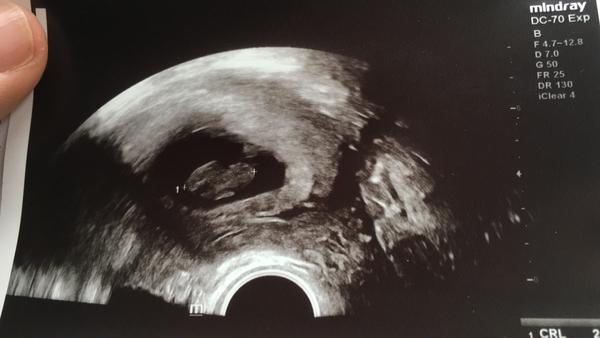

Tak mimčo je v pořádku. Nic nenasvědčuje krvácení.. doktor neví proč krvácím a že s tím stejně nic neudělá. Placenta zasahuje do porodních cest tak možná je to tím 🤷🏻♀️ no případám si vždycky jak hysterka 🙄 ale jsem ráda že je v pořádku.